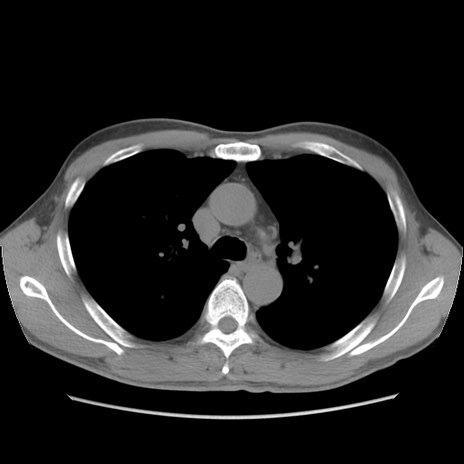

症例56 CT(横断像)

脂肪ウインドウ